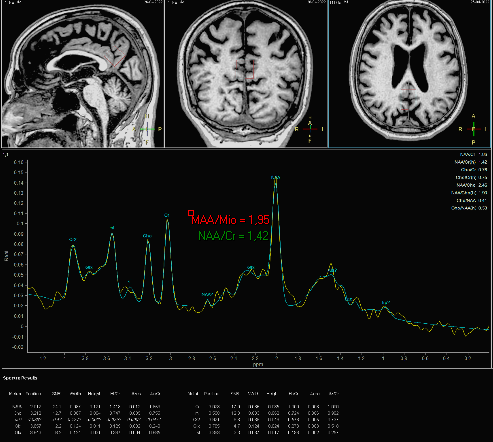

Utilizada com maior frequência no passado, a técnica de espectrospia com voxel único (SV), tem sido usada atualmente como ferramenta adicional na investigação de estados demenciais, colhendo amostras de voxel colocado em diferentes partes do sistema nervoso mais vulneráveis ao processo degenerativo, em especial no cíngulo posterior (doença de Alzheimer), utilizando tempo de echo curto (30ms), para avaliar comportamento do aminoácido Mio-inositol (um aminoácido considerado marcador glial – Mio) e sua relação com a creatina (Mio/Cr) e com o N-Acetil Aspartato (NAA/Mio).

Na espectroscopia de voxel único (SVS ou EVU), o sinal de RM é maior e tem traçado com informações de metabólitos mais precisas, utilizando tempos de echo de 30 e de 144ms. A técnica de voxel único continua importante no diagnóstico de lesões cerebrais com efeito de massa (tumores, processos inflamatórios), porém mais usada para lesões homogêneas e bem delimitadas